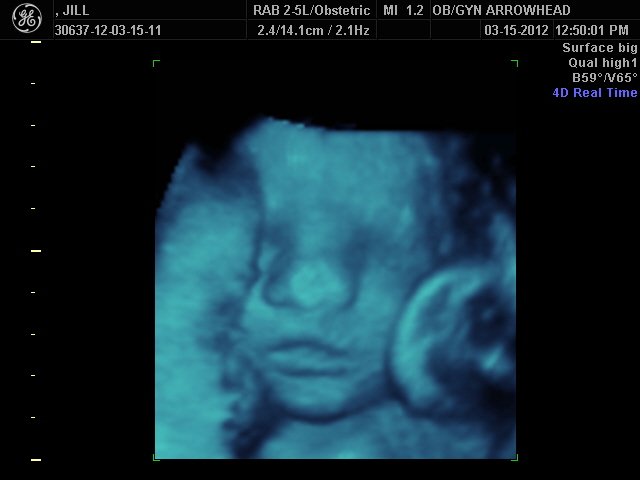

We offer complimentary 3D/4D Ultrasounds to all our OB patients around 30 weeks! The following photos are some examples of our work, shown with permission from our patients.